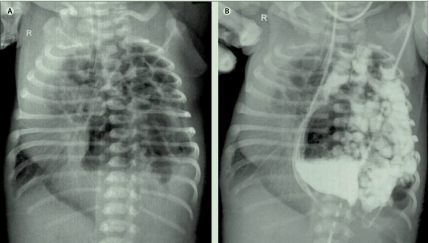

据悉,文章的灵感源于该院多学科团队完成的一次成功的临床救治案例。2017年4月初,一名瘢痕子宫产妇妊娠38周时在中国科大附一院剖腹产生下一名男婴(产前超声考虑为先天性膈疝),孩子在生后不久因呼吸窘迫、发绀而被收入小儿内科新生儿病房,情况危急,医护人员迅速对其进行气管插管和接受高频振荡通气治疗,并进行了床旁X光检查,床旁X线检查能在不搬动病人的情况下,简单快速地对胸部疾病进行初步诊断。结果显示,孩子的左半胸内见肠管影,纵隔向对侧移位,双侧肺严重受压,肺部视野不清,左膈显示不清,因此考虑为先天性膈疝。为了对患儿病情进一步评估,需要立即进行X线造影检查。由于孩子病情危重,传统的钡餐造影检查无法完成,利用新生儿鼻饲胃管,将水溶性碘造影剂注入胃管,为刚刚出生不到一天的患儿快速完成了造影检查,结果显示左侧胸腔内消化道被碘水染色,因此也更加明确了先天性膈疝的诊断。

图左为X线检查,图右是上消化道造影,以此明确膈疝的诊断